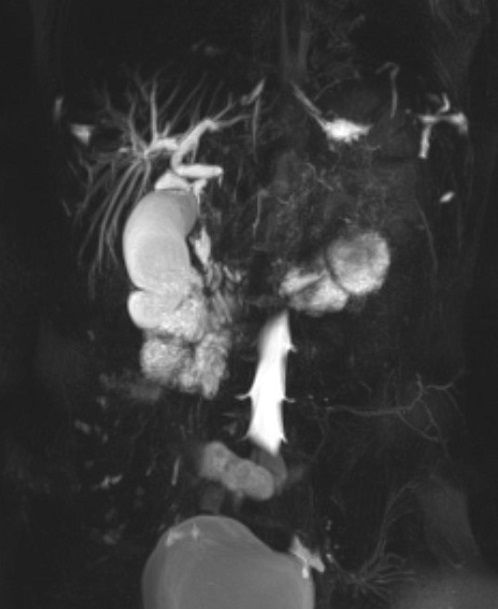

Al mes reaparece la misma sintomatología objetivándose en analítica sanguínea elevación de transaminasas y enzimas de colestasis. Se solicita colangiorresonancia magnética (Fig. 1) con mayor inflamación de la cabeza del páncreas con áreas hemorrágicas y obstrucción completa del colédoco.

| Fig. 1. Colangiorresonancia magnética pancreática con secuencias potenciadas en T2 y difusión. Afectación inflamatoria difusa de páncreas con mayor inflamación de cabeza pancreática condicionando compresión extrínseca sobre colédoco intrapancreático que se encuentra totalmente obliterado |